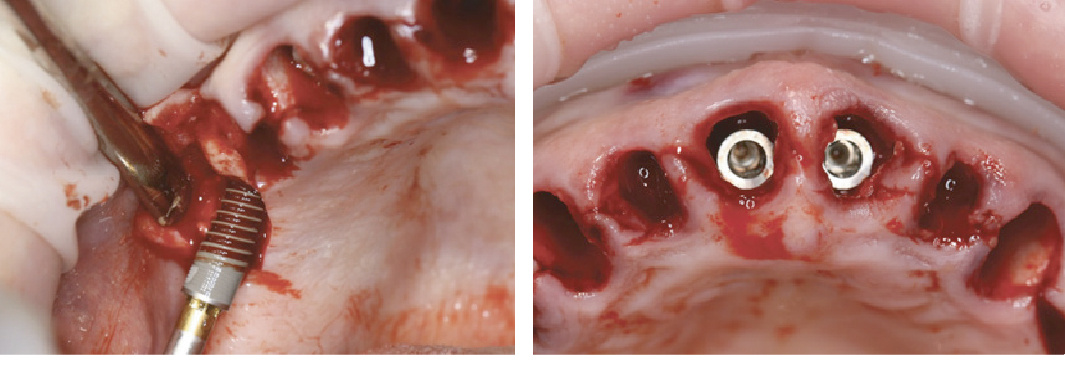

Нами проведено имплантационное протезирование протяженными конструкциями на верхней челюсти трех пациентов. Каждому пациенту непосредственно создавали имплантационные протезы из полимеров в первые 12 часов после операции. Спустя 6 месяцев были фиксированы окончательные металлополимерные протезы. Сохраняемость имплантационных конструкций (включая сохраняемость самих имплантатов) через 36 месяцев составила 100%. На клинических фотографиях (рис. 1—9) представлены существенные клинико-технологические этапы имплантационного протезирования пациентов с использованием компонентов системы «SKY fast & fixed» bredent medical (Senden, Germany) с немедленной нагрузкой.

Рис. 1 Введение имплантатов системы blueSKY fast & fixed bredent medical (Senden, Германия) одномоментно после удаления зубов пациенту 1: а) сперва вводятся дистальные имплантаты; б) нёбное положение центральных опор